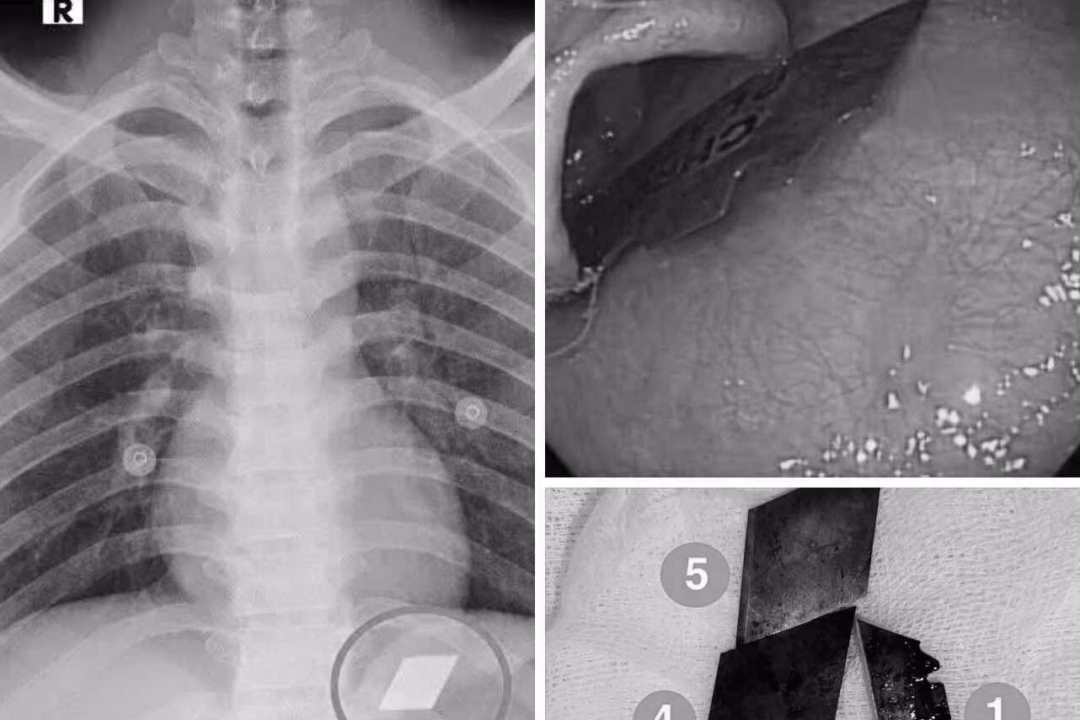

Qua quá trình thăm khám và chụp X-quang, các bác sĩ đã phát hiện ra các dị vật cản quang tại vị trí dạ dày. Nhận định tình hình, bệnh nhân ngay lập tức được chỉ định nội soi cấp cứu để gắp bỏ dị vật. Quá trình này đòi hỏi sự chính xác và cẩn trọng cao để tránh gây tổn thương thêm cho đường tiêu hóa của bệnh nhân.

Dưới sự phối hợp chặt chẽ giữa ê-kíp nội soi và gây mê, các bác sĩ đã thành công trong việc gắp 4 lưỡi dao rọc giấy ra khỏi dạ dày và một phần lưỡi dao lam mắc tại vùng hạ họng – miệng thực quản. Đây là một thủ thuật phức tạp và đòi hỏi kỹ thuật cao, cũng như sự phối hợp nhịp nhàng giữa các chuyên khoa.

Sau thủ thuật, bệnh nhân được theo dõi sát tình trạng sức khỏe và đã ổn định, xuất viện trong tình trạng an toàn. Thành công trong ca xử trí này không chỉ cho thấy vai trò quan trọng của kỹ thuật nội soi can thiệp trong điều trị cấp cứu, mà còn thể hiện sự phối hợp hiệu quả giữa các chuyên khoa và năng lực chuyên môn ngày càng được nâng cao trong việc tiếp nhận và xử trí các tình huống cấp cứu phức tạp.